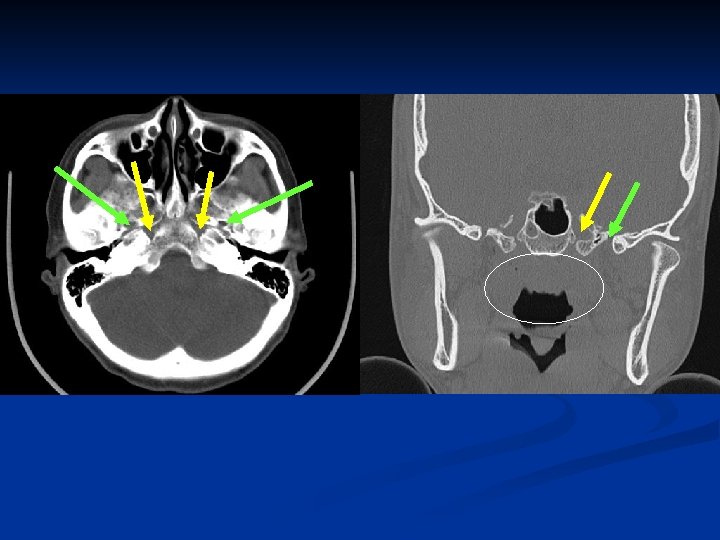

Pterygopalatine fossa (PPF)

Foramen ovale-CN V 3 Foramen lacerum-ICA Foramen lacerum Foramen ovale